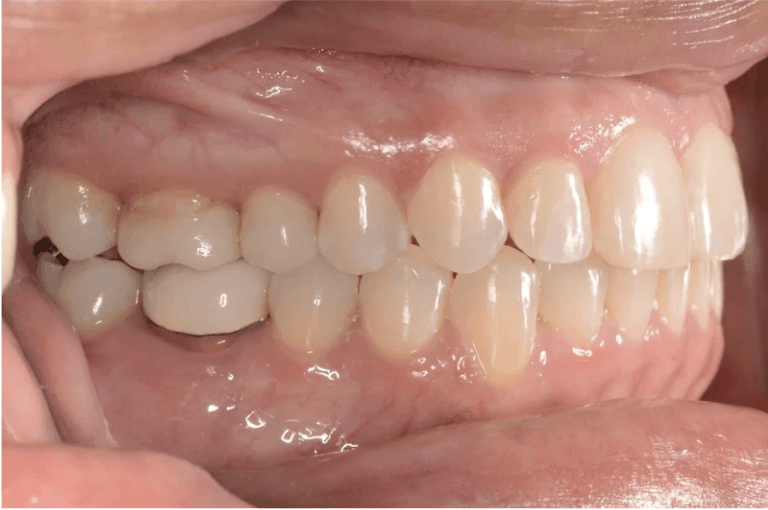

Initial treatment

INTRAORAL

Final results